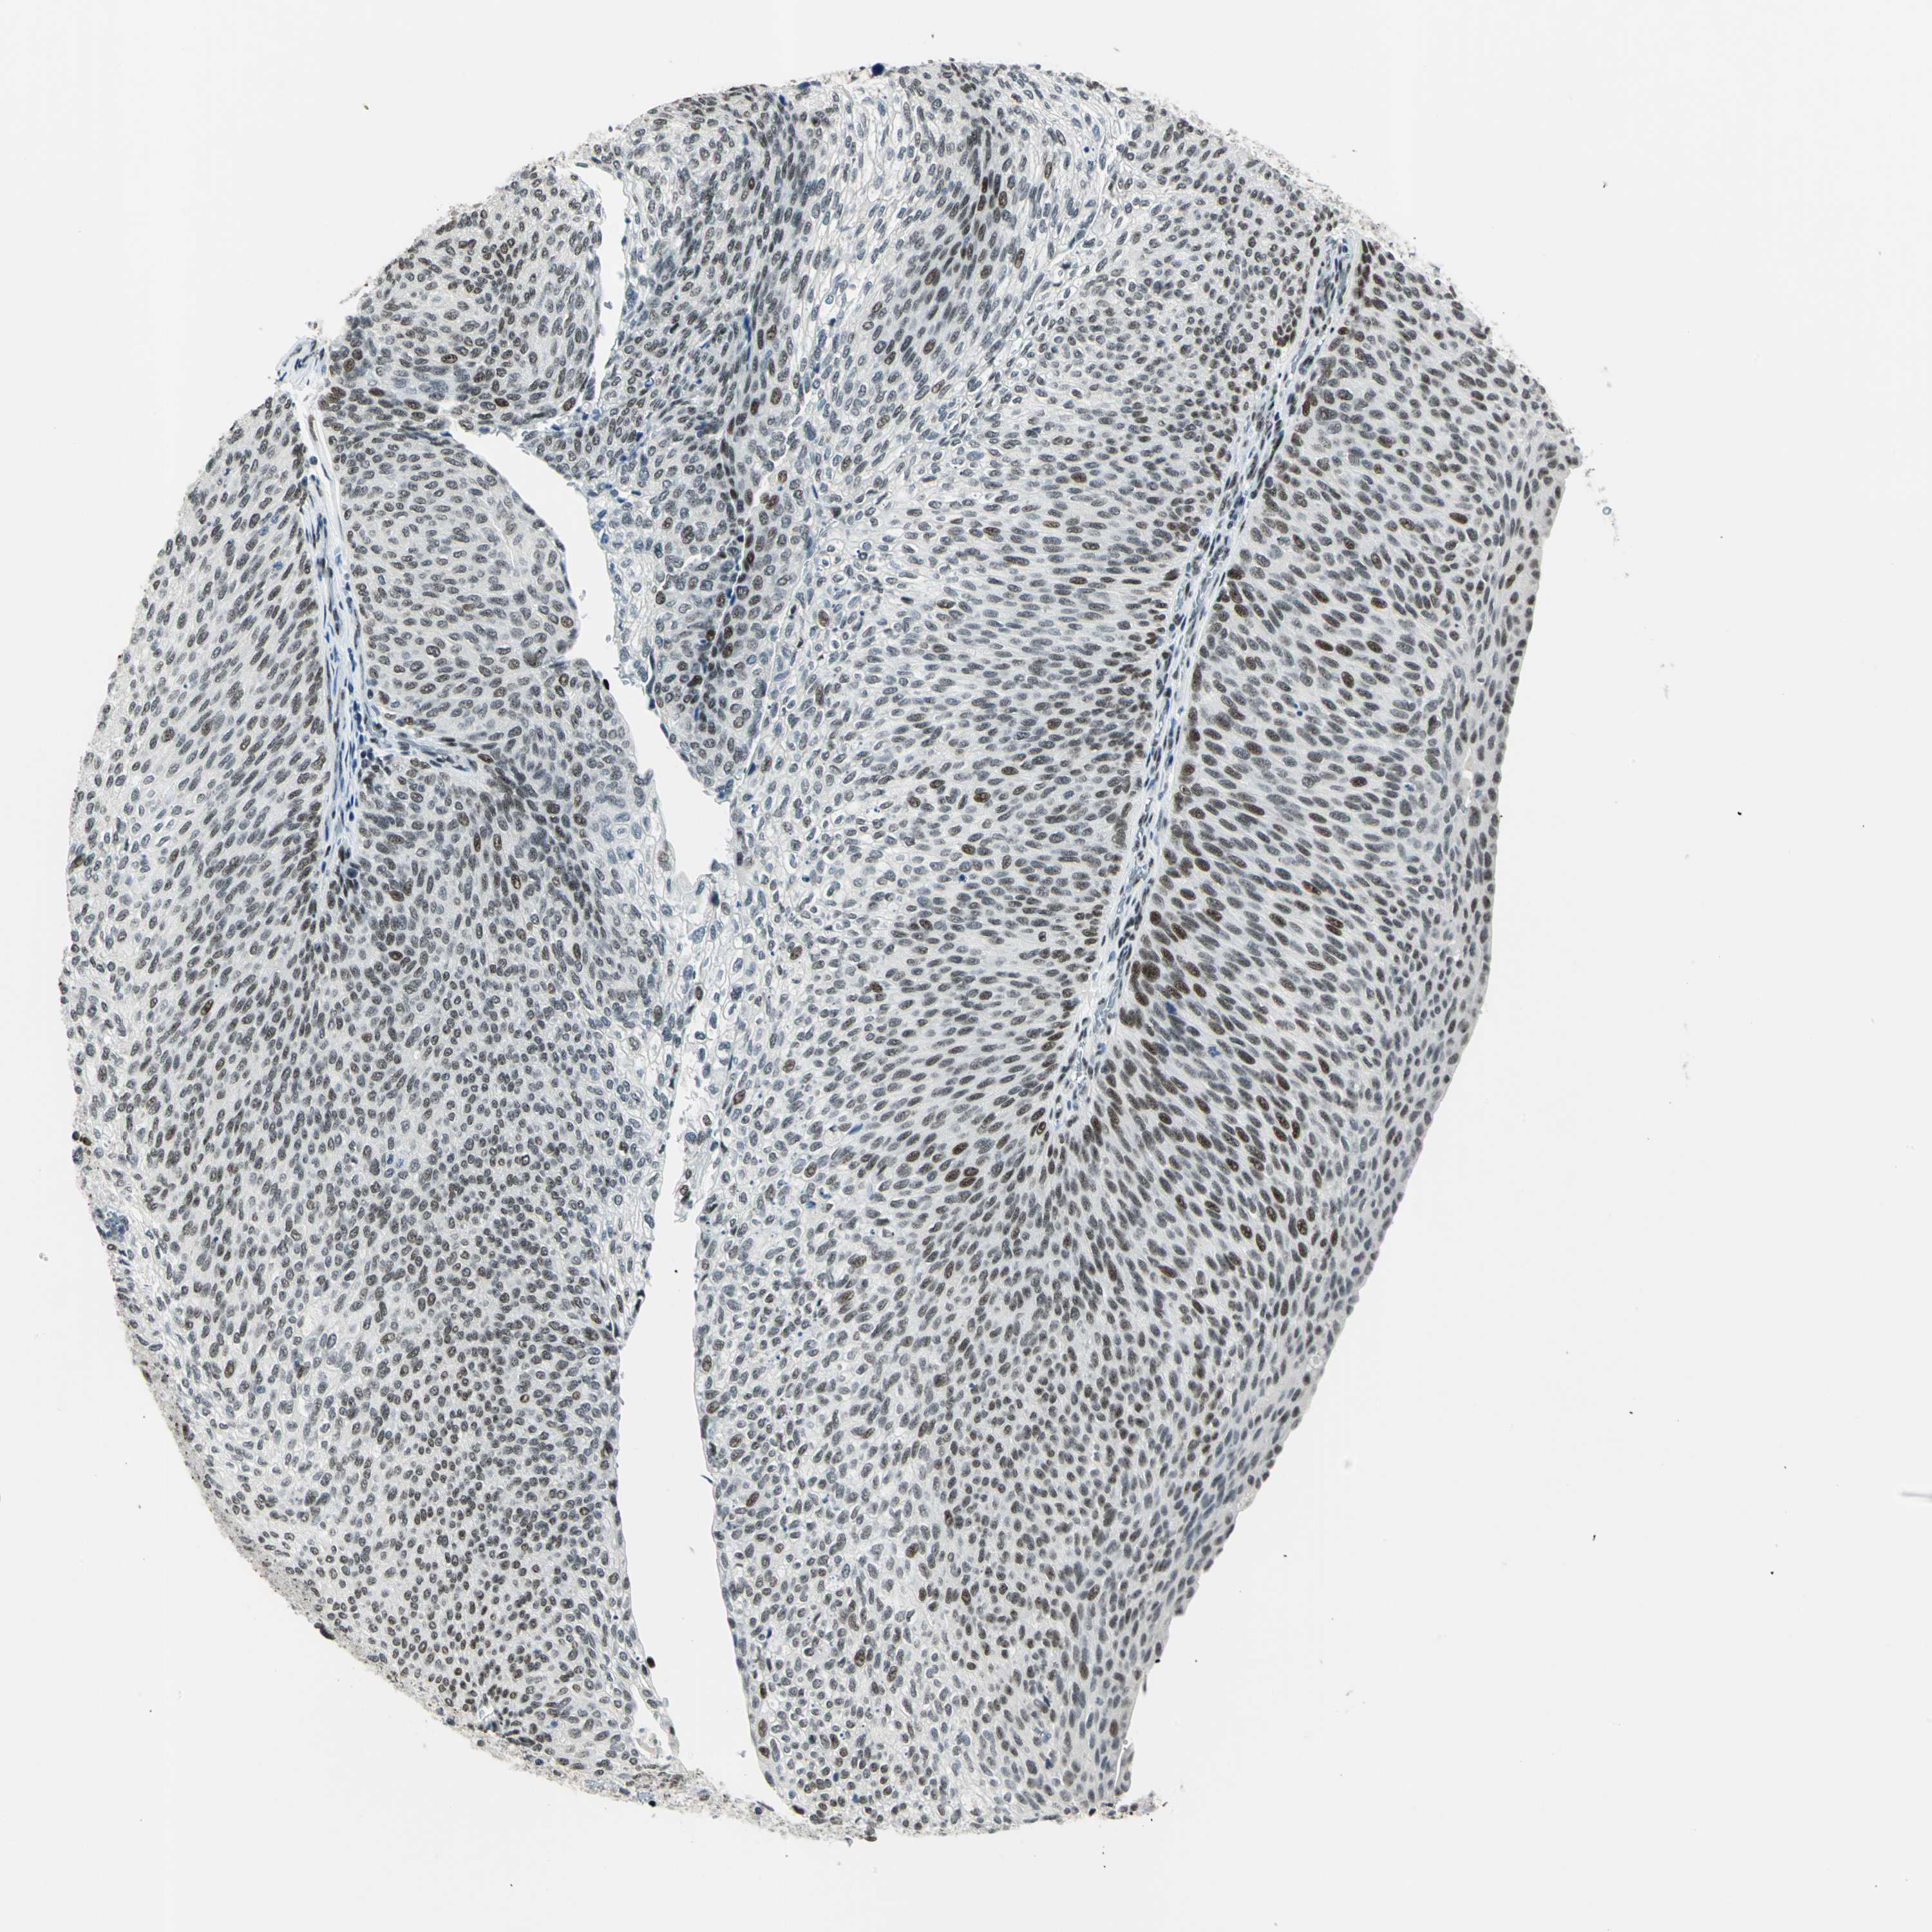

UROTHELIAL CANCER - Protein expressioni

A mouse-over function shows sample information and annotation data. Click on an image to view it in a full screen mode. Samples can be filtered based on level of antibody staining by selecting one or several of the following categories: high, medium, low and not detected. The assay and annotation is described here.

Antibody stainingi

Antibody staining in the annotated cell types in the current human tissue is reported as not detected, low, medium, or high, based on conventional immunohistochemistry profiling in selected tissues. This score is based on the combination of the staining intensity and fraction of stained cells.

Each image is clickable and will lead to virtual microscopy that enables deeper exploration of all samples and also displays staining intensity scores, fraction scores and subcellular localization as well as patient and tissue information for each sample.

Antibody HPA006104

Staining

High

Medium

Low

Not detected

Intensity

Strong

Moderate

Weak

Negative

Quantity

>75%

75%-25%

<25%

None

Location

Nuclear

Cytoplasmic/membranous

Cytoplasmic/membranous,nuclear

Urothelial carcinoma, Low grade

Urothelial carcinoma, High grade